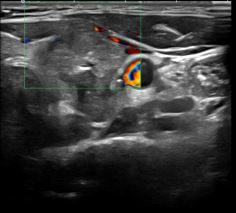

상기환자 목 멍우리 있어 내원하신 40대 후반 여성분으로

의심스러운 갑상선 좌엽 세포검사후 갑상선암으로 진단되었습니다